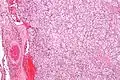

Micrograph of a carotid body tumor

On microscopic inspection, the tumor cells are readily recognized. Individual tumor cells are polygonal to oval and are arranged in distinctive cell balls, called Zellballen.[8] These cell balls are separated by fibrovascular stroma and surrounded by sustentacular cells.

By light microscopy, the differential diagnosis includes related neuroendocrine tumors, such as carcinoid tumor, neuroendocrine carcinoma, and medullary carcinoma of the thyroid.